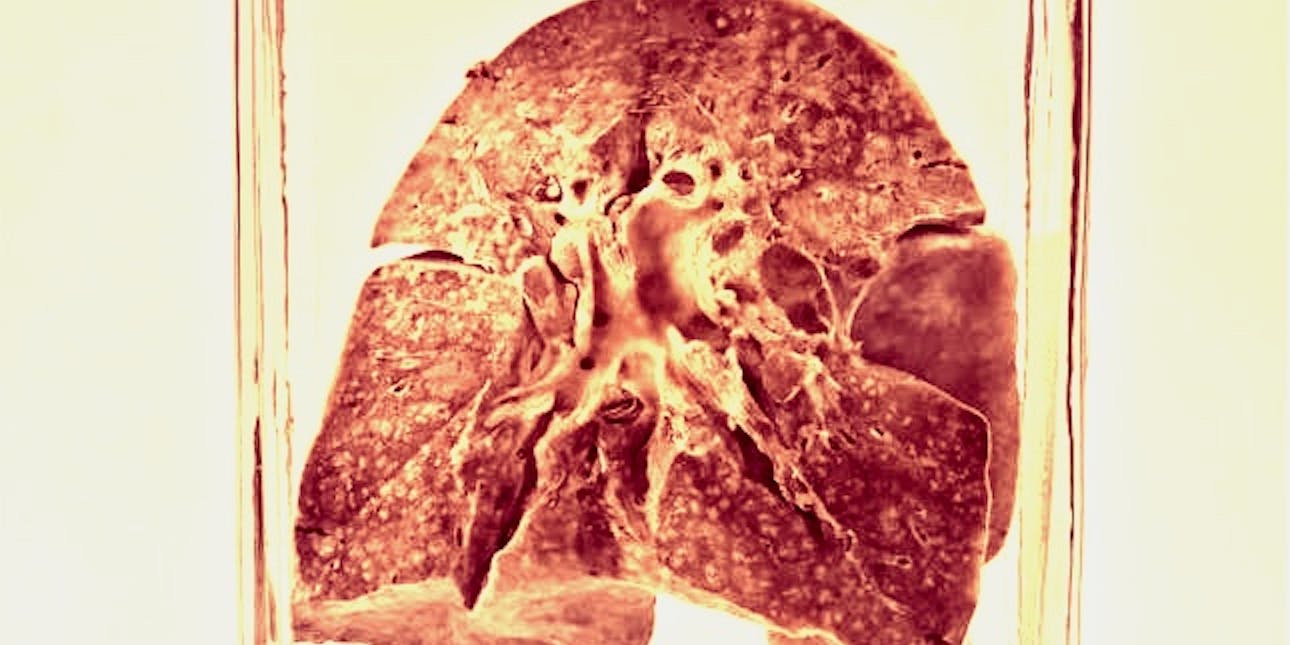

The lungs were originally collected during an autopsy after their original owner died of measles-related bronchopneumonia on June 3, 1912, according to the paper’s supplementary material. Then, they remained untouched for over a century.

As Science magazine reported, these lungs were found by the study’s senior author Sébastien Calvignac-Spencer in a basement at the Berlin Museum of Medical History. That museum is already known for a collection of organs suspended in jars, reminiscent of Snape’s potion classroom.